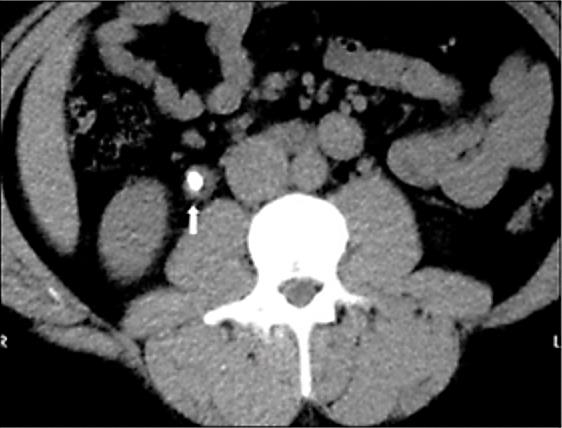

Mulher, 78 anos, portadora de hipertensão arterial sistêmica, diabetes mellitus tipo 2, doença renal crônica estágio II (creatinina basal 0,8 mg/dL), infarto agudo do miocárdio há dois anos com necessidade de angioplastia e tratamento de infecção urinária por uma Serratia sp. produtora de ESBL (Beta-Lactamase de Espectro Estendido) há seis meses. Refere há dez dias disúria e polaciúria, evoluindo há três dias com lombalgia à direita e febre aferida de 38,2ºC. Dá entrada na sala de emergência confusa, hipotensa, taquicárdica, tempo de enchimento próximo a três segundos, levemente taquipneica, sem desconforto, porém com dor à palpação difusa de abdome, pior em fossa ilíaca direita. Coletadas hemocultura, urocultura e exames séricos na urgência. Você chega para o plantão noturno e o plantonista do dia te mostra a tomografia recém realizada (Figura 10) e refere que não teve tempo de checar os exames laboratoriais ou prescrever antibiótico para a paciente.

Hb 14,0 g/dL; Leucócitos 16.500 mil/mm3 com desvio até metamielócitos; Ureia 102 mg/dL; Cr 1,80 mg/dL; Sódio 139 mEq/L; Potássio 5,1 mEq/L; Bilirrubina Total 1,2 mg/dL; Bilirrubina Indireta 0,20 mg/dL; Bilirrubina Direta 1,0 mg/dL; TGO 45 U/L (< 31 U/L); TGP 40 U/L (< 31 U/L); Gama-GT 32 U/L (5 - 36 U/L); Fosfatase Alcalina 67 U/L (35 - 104 U/L); Albumina 3,7 g/dL (3,4 - 4,8 g/dL); INR 1,1.

Figura 10. Tomografia computadorizada sem contraste de abdome

Assinale a alternativa com a conduta mais adequada para este paciente neste momento.